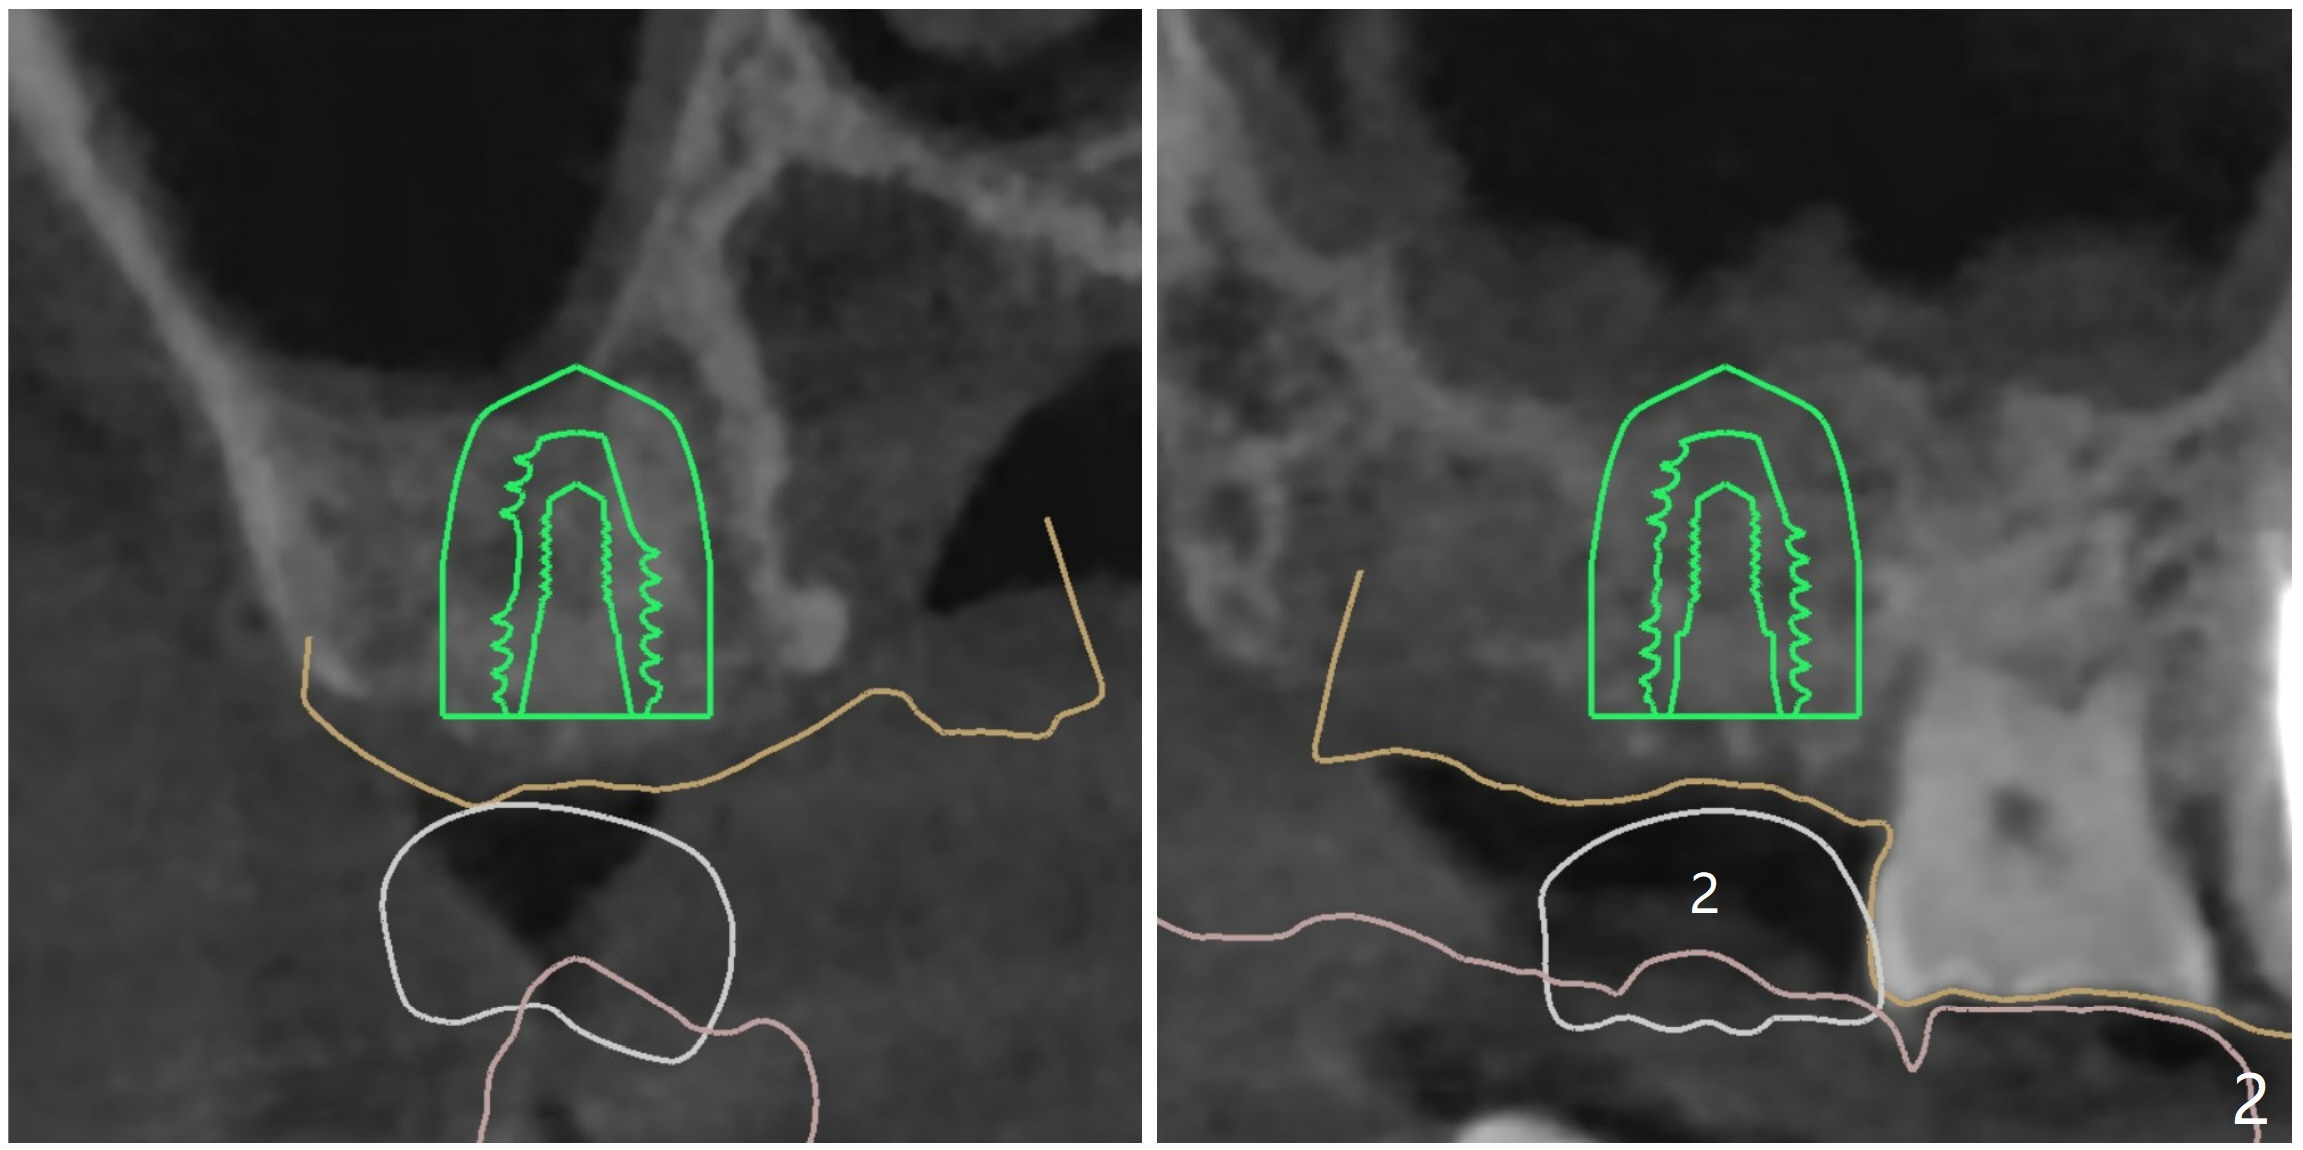

2号牙位点保存后6个月,而15号牙拔除没有植骨1-2年前(图一)。2号牙位骨质高度足够,准备不做上颌窦提升(图二),而15号牙位需要提升(图三,六)。种植术后5个月两个植体愈合均正常(图十一,十二)。